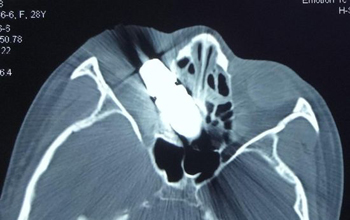

近日,一中心院眼科为一患者成功取出了扎进眼珠的大块金属管。据悉,该患者女,28岁,被高速飞出的金属管扎入眼中,患者受伤后十分着急,赶紧到一中心挂急诊。经检查发现患者右眼眼球壁内侧破裂。CT检查见长约4CM金属管状异物斜上插入眶内,眼球结构破坏,眶内壁骨折,鼻骨中隔穿孔。

手术前CT